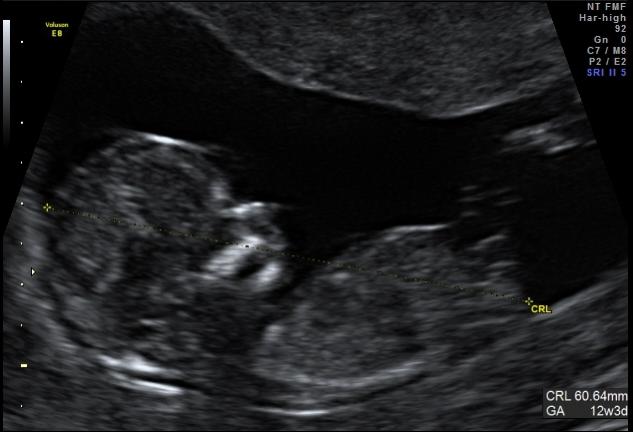

I have attached two profile shots from my 12w3d scan and although I have read a bit on nub theory I really cant tell if there is even a nub there or if its just part of the cord. Would anyone like to put their opinion forward :bigsmile:

Attachment 116Attachment 117